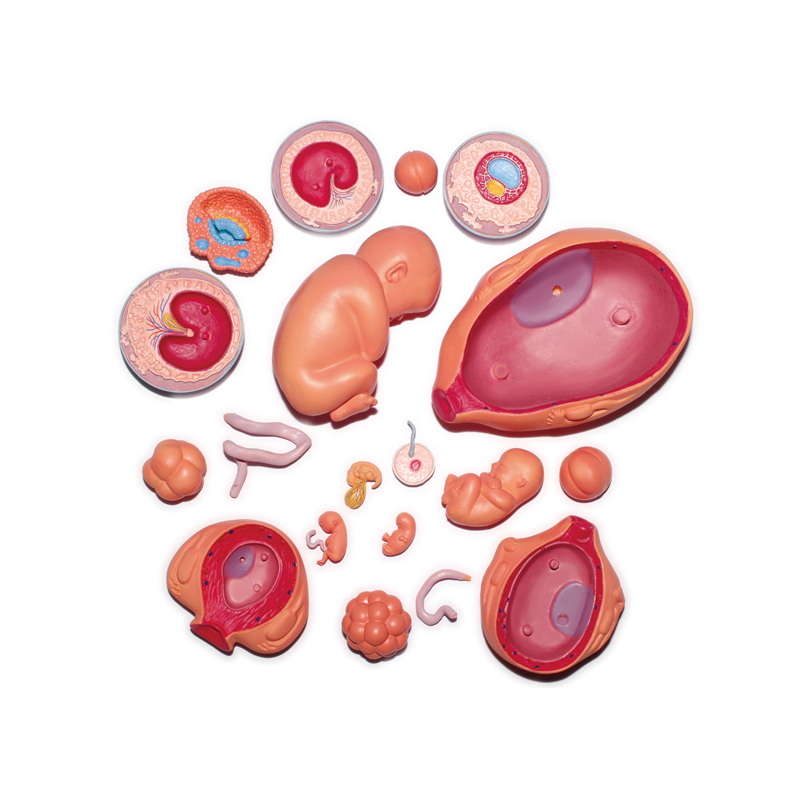

4D MASTER Human Anatomy Premium Embryo Development, Fertilisation to Fetus Development